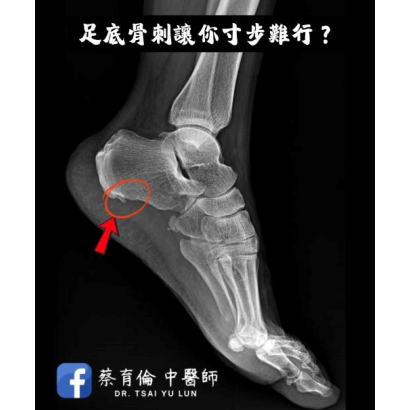

足底筋膜炎合併足跟骨刺案例分享,小針刀鬆解筋膜張力,改善晨起第一步刺痛與久站疼痛問題。

起床第一步刺痛像踩釘子?常見足底筋膜炎與跟骨骨刺,經醫師評估後以針灸與小針刀協助改善疼痛與行走不適。